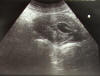

Quiste sinovial muñeca. Eco.

ECO cálculos en vías biliares

MO Ectasia pielocalicial.